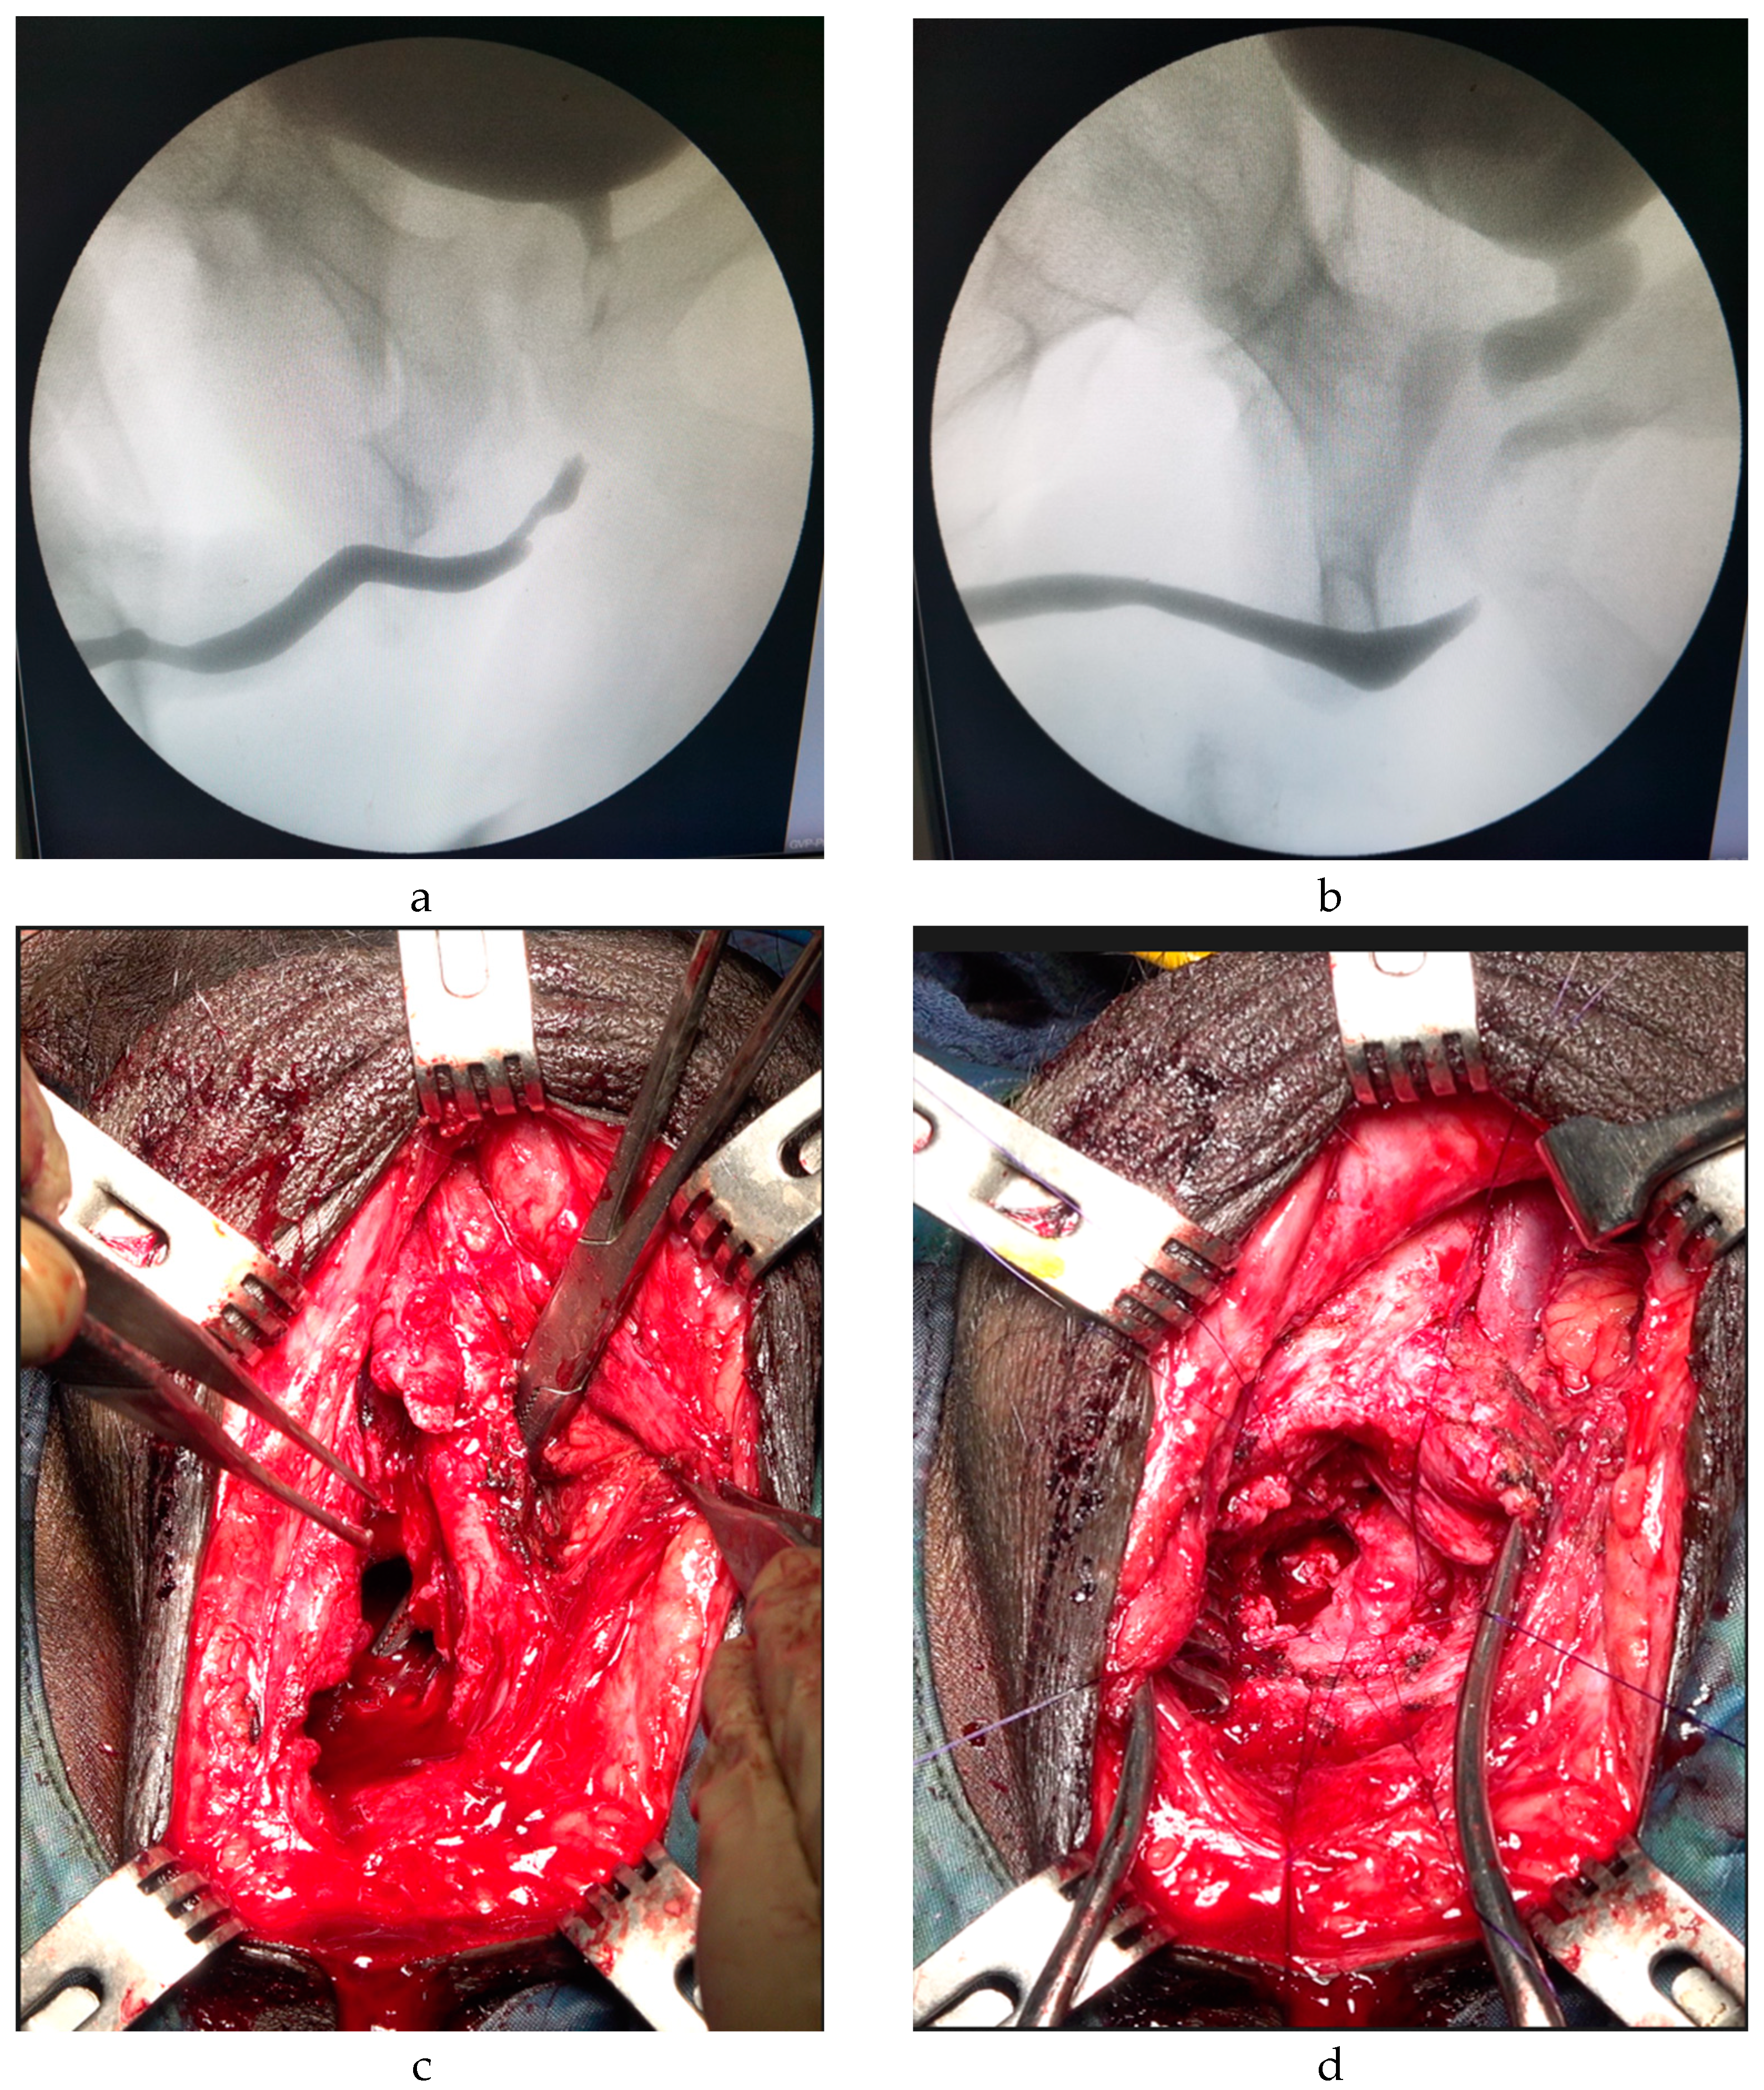

| Supracrural urethral rerouting | 13 (1.8%) | 9 (69.2%) |

| Primary cases Redo cases | 2 (15.4%) 11 (84.6%) |

| Erectile dysfunction | 6 (46.1%) |

| Success rate Recurrence Final success rate | 9 (69.2%) 4 (30.8%) 11 (84.6%) |